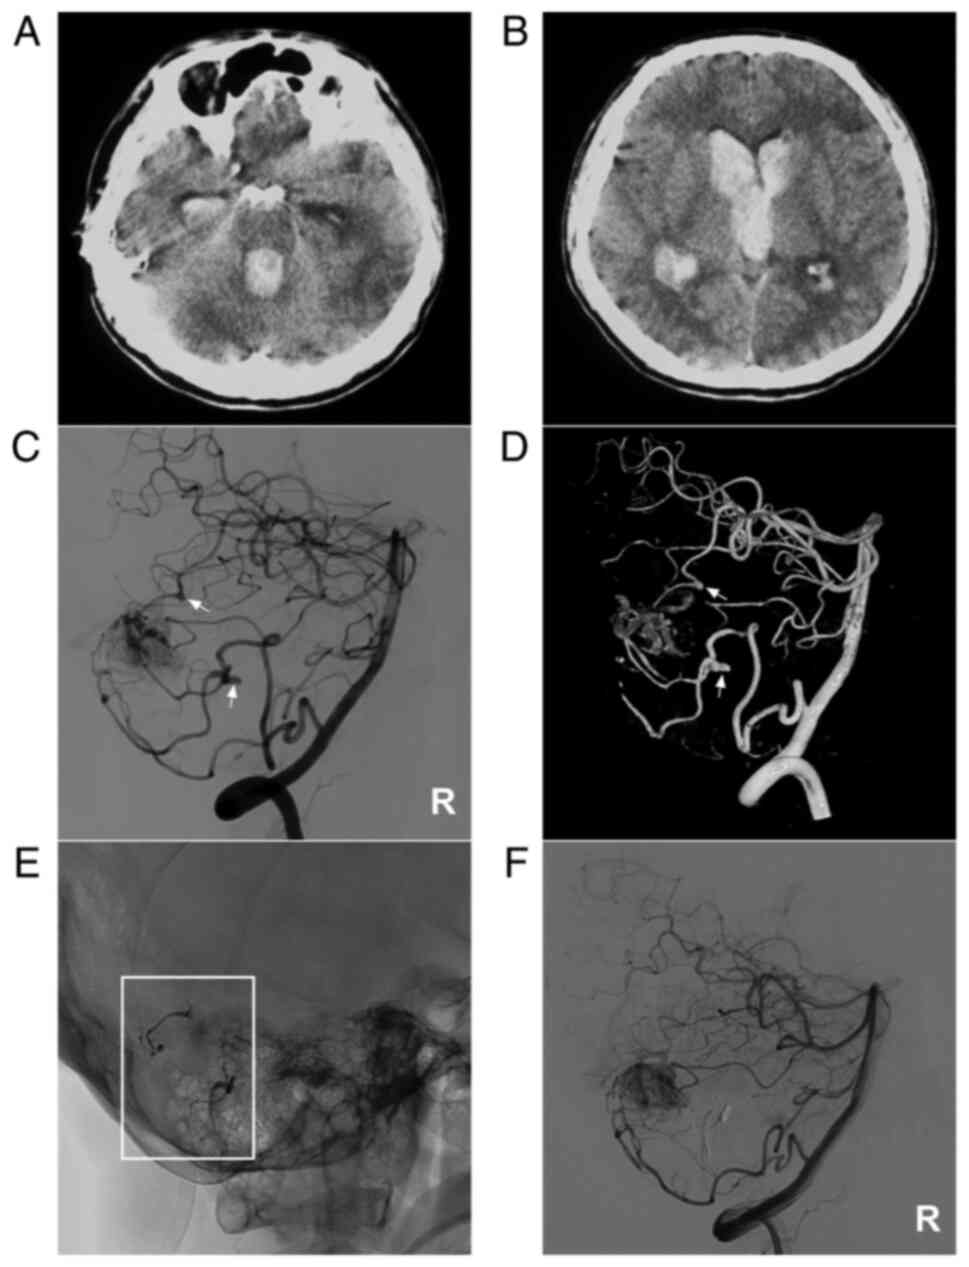

Figure 6

AVM combined with multiple prenidal aneurysms on the SCA and PICA. (A and B) Brain CT scan showing (A) fourth ventricular hemorrhage and (B) lateral ventricular hemorrhage. (C) Two-dimensional and (D) three-dimensional DSA of the vertebral artery showing that multiple aneurysms (arrows) can be observed on the SCA and PICA. (E) X-ray film showing Onyx™ casting (square box) in the aneurysms. (F) DSA of the right vertebral artery showing that the aneurysms were not observed. The case presented in this figure was a 38-year-old male. He developed a headache and then fell into a coma. Following external ventricular drainage, he recovered well and underwent EVT. No EVT complication was observed. The patient currently appears almost normal. AVM, arteriovenous malformation; CT, computed tomography; DSA, digital subtraction angiography; PICA, posterior inferior cerebellar artery; R, right; SCA, superior cerebellar artery.